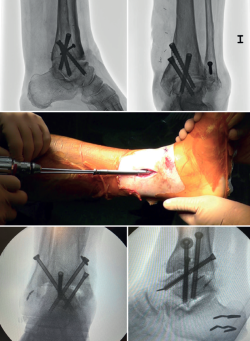

En las artrodesis de tobillo por vía artroscópica, el uso de tornillos a compresión colocados de forma percutánea es la técnica de elección (Figura 5).

La mayoría de los autores consideran el uso de tornillos canulados (de 3 a 4) como el método idóneo de fijación. Los diámetros de los tornillos escogidos oscilarán entre los 6 y los 7 mm. Con esta técnica se consigue del 85 al 100% de fusión y entre el 84 y el 95% de satisfacción del paciente(19).

Van Dijk, Kerkhoffs et al.(20) reportan excelentes resultados con el uso de 3 tornillos como método estandarizado para las artrodesis de tobillo.

Configuración y colocación de los tornillos

Dependiendo de la deformidad y en función de la planificación preoperatoria, se realiza la colocación de los tornillos, comenzando con el tornillo de compresión que contrarresta la deformidad.

Es decir, en las artropatías con componente de varo empezaríamos por un tornillo lateral, mientras que en las desalineaciones en valgo la recomendación es colocar el primer tornillo desde medial. El segundo tornillo debería ser del lado opuesto al primero. Ambos deben realizar la compresión adecuada entre superficies articulares(17).

En general, se utilizan un mínimo de 3 tornillos. El tercer tornillo es el denominado home run, cuya importancia destacan en su trabajo Holt et al.(21). Se dirige cruzando el tobillo desde la parte posterior de la tibia hasta el cuello del astrágalo. Puede utilizarse un cuarto tornillo a modo de aumentación del primero, del que contrarresta la deformidad principal.

Goetzmann et al.(22), en su serie de revisión de 111 casos, respaldan el uso de al menos 3 tornillos para la fijación de la artrodesis tibioastragalina artroscópica. Añadir un tercer tornillo parece asociarse con un menor riesgo de pseudoartrosis y un menor tiempo de consolidación. Estos efectos pueden atribuirse a una mayor estabilidad del constructo.

Glick, Myerson(23) et al. publicaron que la configuración que conferiría mayor rigidez a la osteosíntesis es con 2 tornillos desde medial y 1 desde lateral.